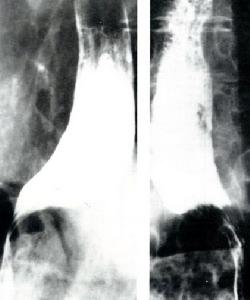

1.硬皮病 X線檢查十二指腸和近端空腸擴張具有特徵性,有時整個小腸擴張,環狀皺襞往往增粗。充鋇腸腔邊緣呈毛刺狀。

3.結節性多動脈炎 X線檢查顯示小腸黏膜紊亂、潰瘍、息肉狀增生、節段性狹窄等,也酷似局限性腸炎或非特異性潰瘍性結腸炎的X線表現。